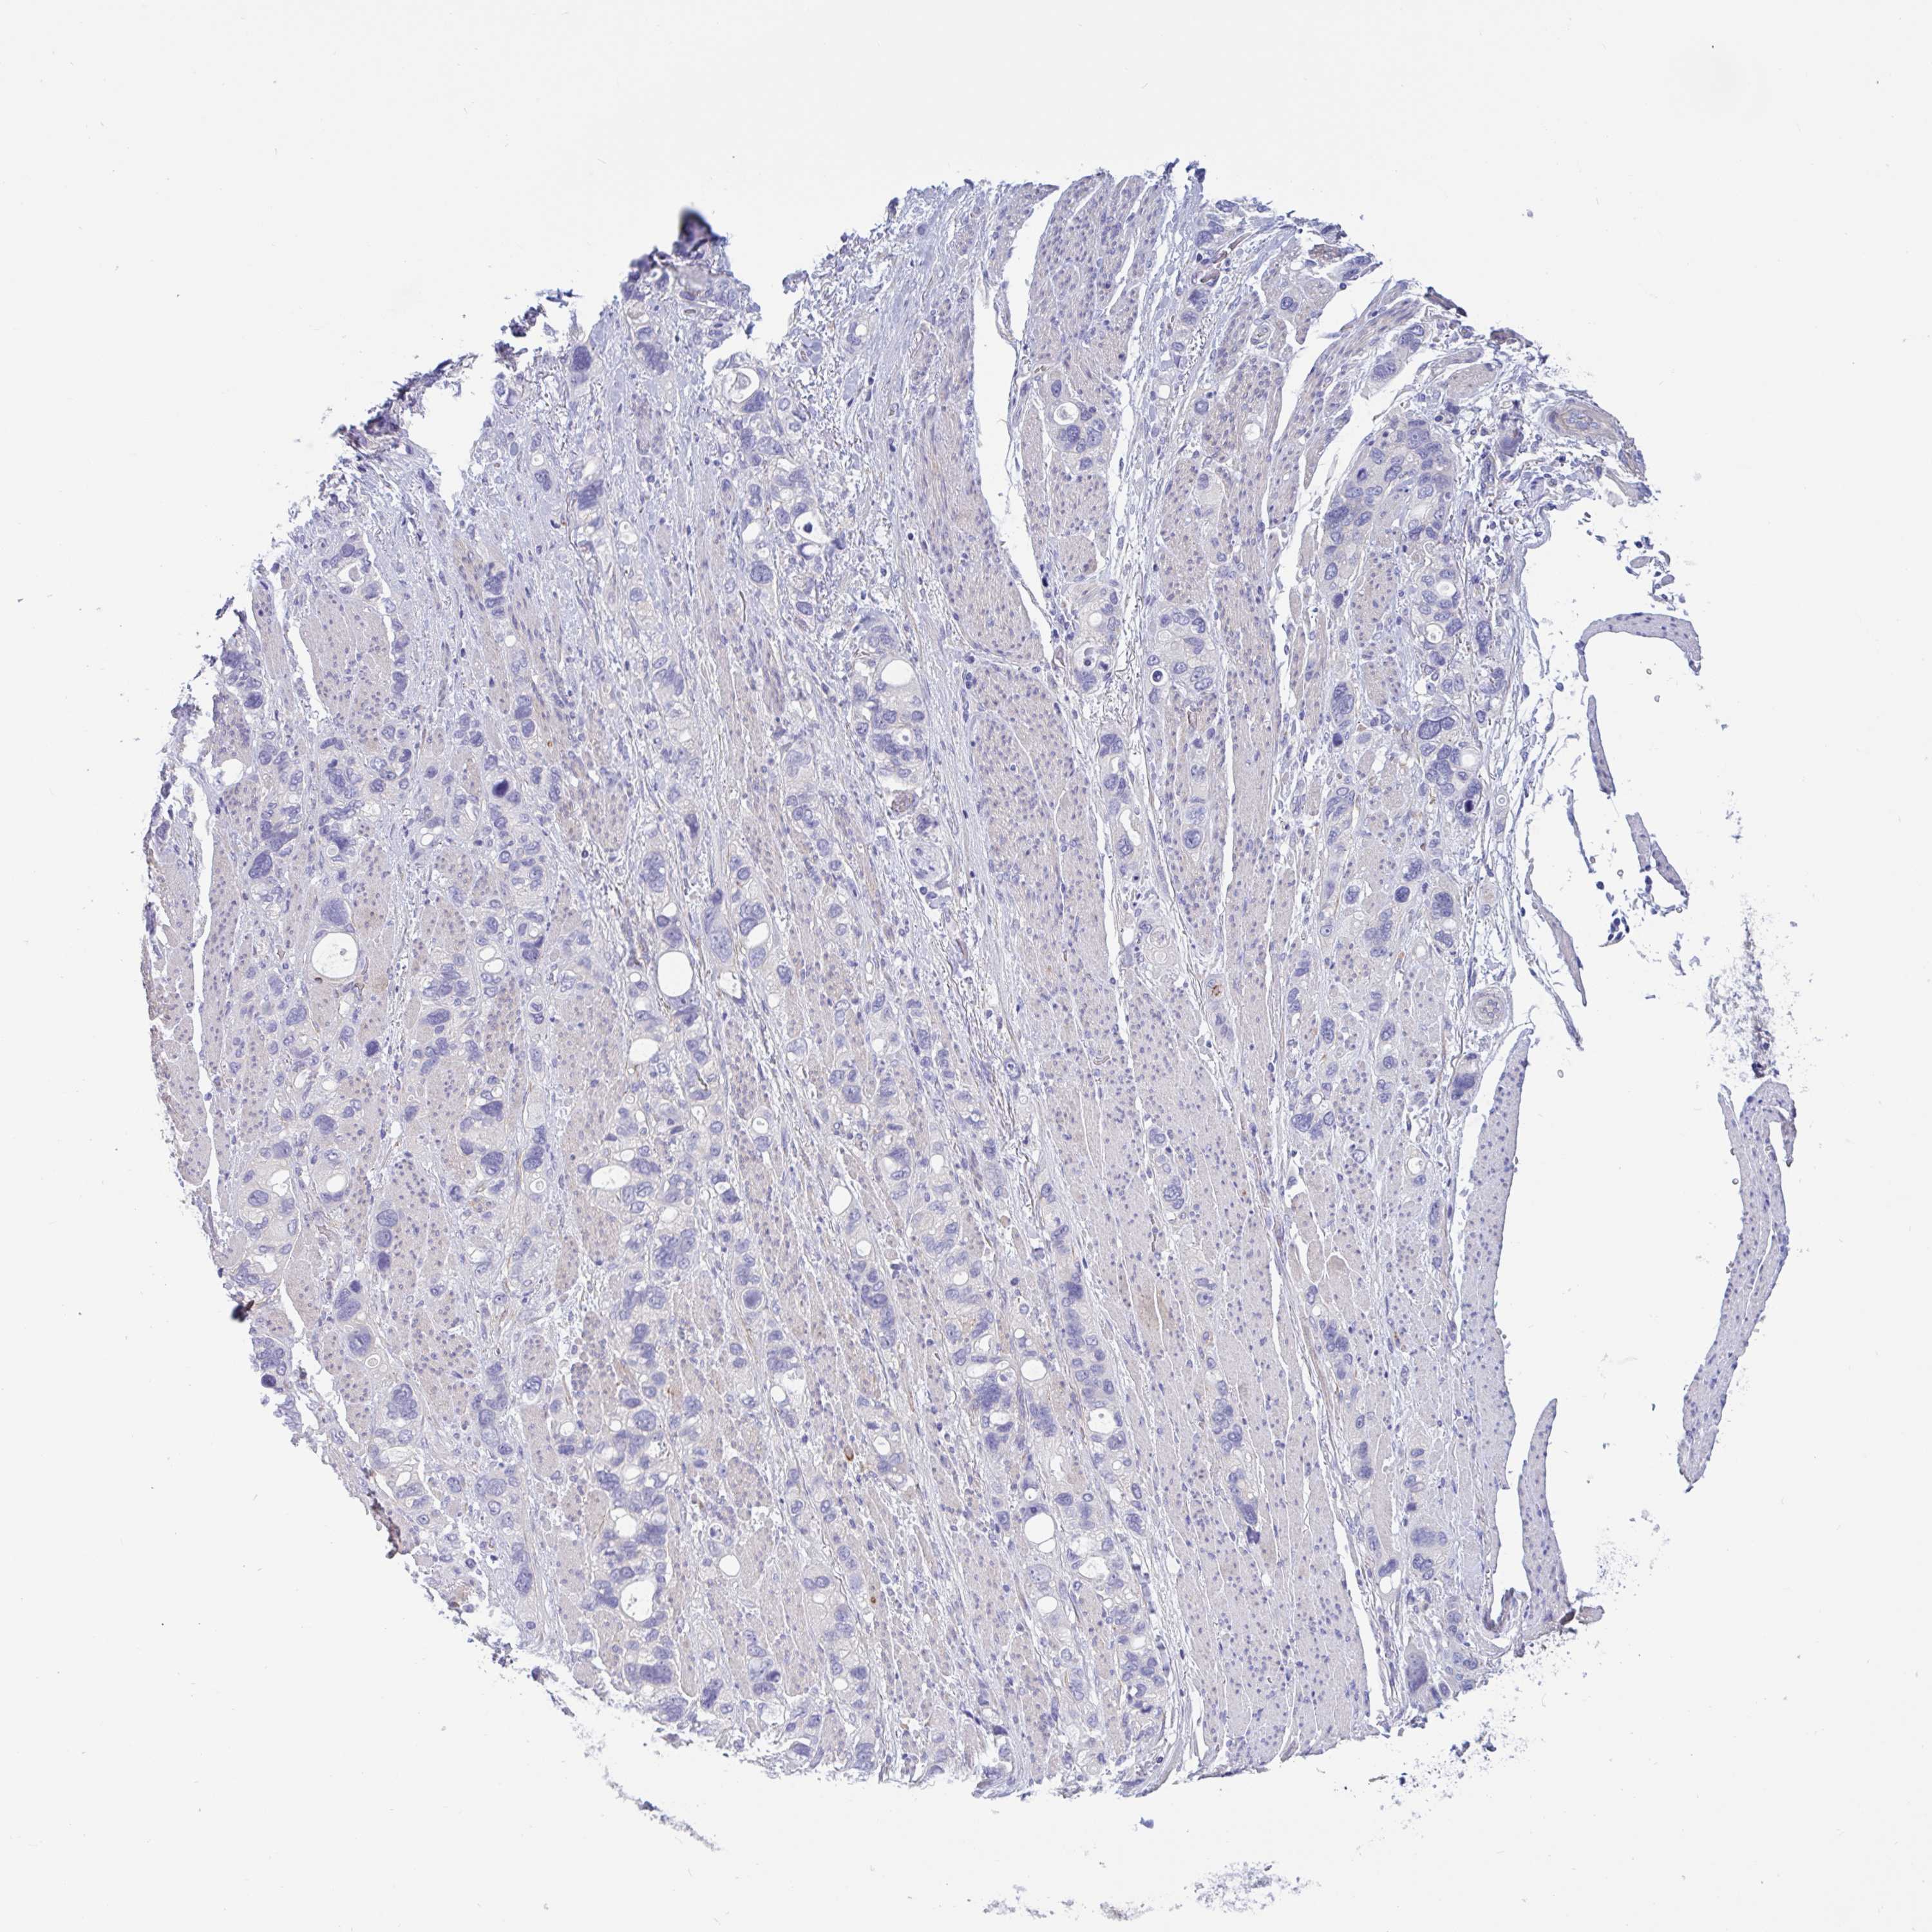

STOMACH CANCER - Protein expressioni

A mouse-over function shows sample information and annotation data. Click on an image to view it in a full screen mode. Samples can be filtered based on level of antibody staining by selecting one or several of the following categories: high, medium, low and not detected. The assay and annotation is described here.

Note that samples used for immunohistochemistry by the Human Protein Atlas do not correspond to samples in the TCGA dataset.

Antibody stainingi

Antibody staining in the annotated cell types in the current human tissue is reported as not detected, low, medium, or high, based on conventional immunohistochemistry profiling in selected tissues. This score is based on the combination of the staining intensity and fraction of stained cells.

Each image is clickable and will lead to virtual microscopy that enables deeper exploration of all samples and also displays staining intensity scores, fraction scores and subcellular localization as well as patient and tissue information for each sample.

Antibody HPA056878

Antibody HPA057019

Staining

High

Medium

Low

Not detected

Intensity

Strong

Moderate

Weak

Negative

Quantity

>75%

75%-25%

<25%

None

Location

Nuclear

Cytoplasmic/membranous

Cytoplasmic/membranous,nuclear

Adenocarcinoma, NOS